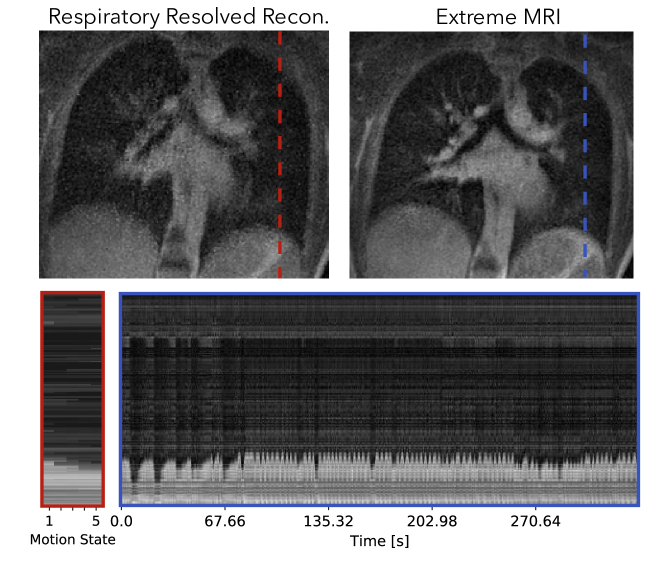

We applied the proposed reconstruction on two lung datasets from adult patients to qualitatively evaluate its performance. All datasets were acquired on GE 3T Discovery MR750 clinical scanners (GE Healthcare, Waukesha, WI) using an optimized UTE sequence [1] and a bit-reversed ordered 3D radial trajectory. The first dataset has regular respiratory motion and little bulk motion. The second dataset has abrupt bulk motions such as coughing throughout the scan.

We compared the proposed method with respiratory resolved reconstruction to five motion states. The proposed technique was reconstructed with 500 frames, whereas for the third lung dataset. The respiratory resolved reconstruction was performed with total variation regularization along the motion states, which is similar to Jiang et al. [2] and Feng et al. [54]. To exclude data corrupted by bulk motion, only k-space data with the respiratory signal between the 10th and 90th percentiles were used. They were then sorted into five equally sized bins, each representing a motion state.

Figure 10 and Supporting Information Video S13 and S14 compare the proposed method with the respiratory-resolved reconstruction. From the cross-section and Supporting Information Video S13, coughing can be observed in the beginning of the scan for the proposed reconstruction. The patient can be seen to return to a more regular breathing pattern after a while but still occasionally show abrupt motions. The proposed reconstruction does show flickering temporal artifacts when the patient coughs, but in general has less noise-like artifacts and much sharper features than the respiratory resolved reconstruction.

An instance of the proposed method takes about 11.5 hours and the respiratory resolved reconstruction takes about 15 minutes. The resulting image using the MSLR representation takes 2.8GBs to store.

Figure 10 shows that for pulmonary imaging, the proposed reconstruction really shines when there are non-periodic motions. Because Figure 9 mostly consists regular breathing, the proposed reconstruction does not offer much beyond unrolling the periodic dynamics. However, for the second dataset with irregular breathing, the proposed reconstruction provides substantially improved image quality, and also depicts the irregularities. In particular, coughing can be seen from the beginning of the dynamic image series.